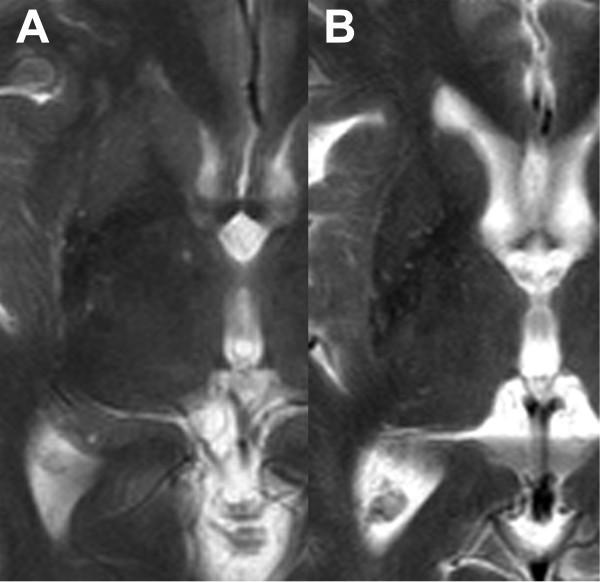

HPR was observed in 38.5% of normal subjects. Age and gender predilection and laterality were not observed. In most cases, it occupied the full length or anterior half of the lateral margin of putamen, and was continuous throughout its length. Maximum transverse dimension was 2 mm. There was no association with hypointensity of nearby putamen. However, in MSA-P, HPR was located predominantly at the posterolateral aspect of putamen, and associated with putaminal atrophy. Discontinuity of HPR was more frequently observed in MSA-P. On visual analysis, the characteristics of HPR were similar between MSA-C patients and normal subjects. Patients with MSA of either type had significantly higher MD values of putamen than normal subjects.

HPR can be observed in 38.5% of normal subjects at 1.5 T. Thin linear hyperintensity without discontinuity, occupying the full length or anterior half of the lateral margin of the putamen, is suggestive of "normal." In doubtful cases, measurement of the MD values of nearby putamen may be valuable.

38.5%的正常人群中观察到 HPR。HPR 无年龄和性别分布差异,也无侧别差异。HPR 多占据壳核外侧缘全长或前半段,连续性好。最大横径 2mm。与临近豆状核低信号无相关性。但在 MSA-P 患者中,HPR 多位于壳核的后外侧,与壳核萎缩相关。HPR 连续性中断在 MSA-P 中更常见。在视觉分析中,MSA-C 患者的 HPR 特征与正常人群相似。两种类型的 MSA 患者的壳核 MD 值均显著高于正常人群。

在 1.5T 场强下,38.5%的正常人群中可以观察到 HPR。无连续性中断的细线性高信号,占据壳核外侧缘全长或前半段,提示为“正常”。对于可疑病例,测量临近壳核的 MD 值可能有帮助。